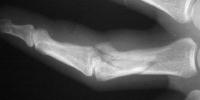

The joint was reconstructed with 1.0mm screws and the shaft fixed with 1.3mm screws using the Synthes titanium modular hand tray.

Intraoperative fluoroscopy.